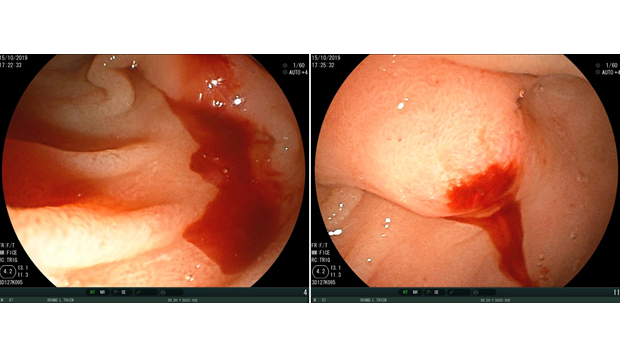

Can thiệp nội mạch cấp cứu một trường hợp vỡ túi giả phình động mạch lách ở bệnh nhân viêm tụy mạn tại Bệnh viện Trường Đại học Y Dược Huế

Bệnh nhân Hoàng Lương T, nam 67 tuổi, được chuyển đến Bệnh viện Đại học Y Dược Huế ngày 15/10/2019 với triệu chứng đi cầu phân đen đã hơn 1 tháng. Bệnh...